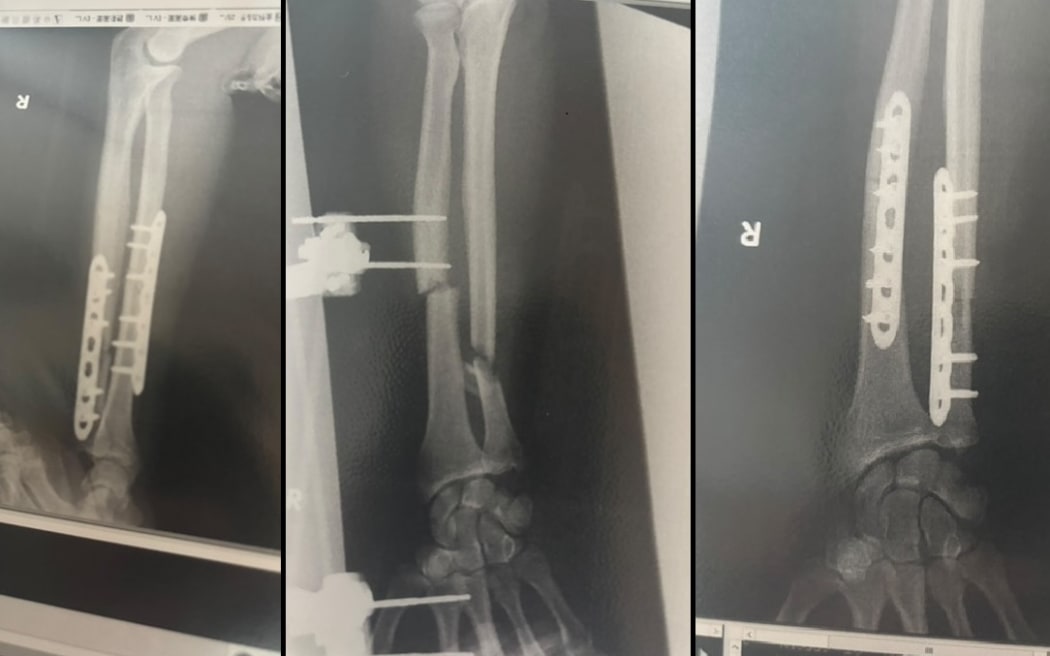

X-rays showing the repair work on Billy Halloran's arm.

X-rays showing the repair work on Billy Halloran's arm. Photo: Supplied

Halloran is recovering this week in Joetsu Hospital after his third surgery. This four-hour procedure involved a hip bone graft. His arm had been broken in three places by the bear, with a chunk taken out of the bone, just from one bite.

He was under general anaesthesia at that time, but just local for the first two surgeries, where he could view a live X-ray to watch the surgeons piece his arm back together and insert a mechanism to clean inside the bone preventing infection.

He now has two metal plates in his arm and four nurses a day checking in on him. His mum flew over from New Zealand, loaded with Whitaker's chocolate.